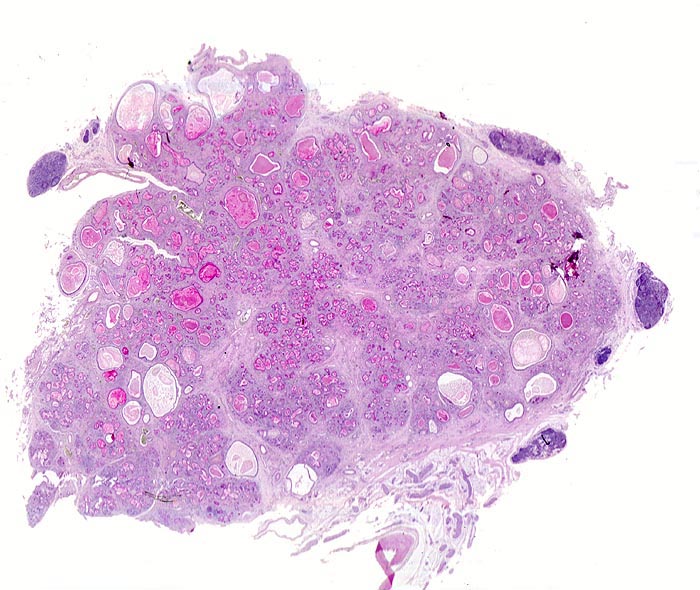

Neben einer mässig ausgeprägten Fibrose fallen in der Übersicht vor allem die zahlreichen dilatierten und mit eingedicktem PAS positivem Schleim angefüllten Gänge auf. Die dunkelblauen Knoten im peripankreatischen Gewebe entsprechen dort üblicherweise vorhandenem lymphatischem Gewebe.

Der Patient verstarb an einer Pneumonie. Es bestand eine Insuffizienz des exokrinen Pankreas mit Malabsorption.